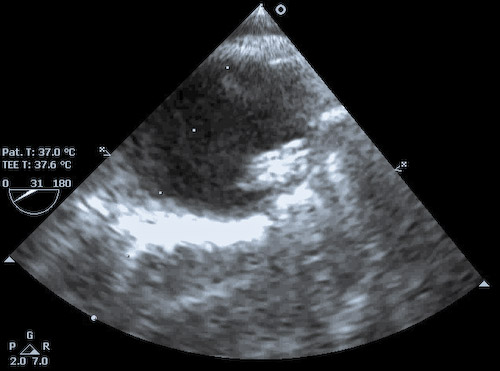

The figure to the left shows an IABP positioned slightly too high with the tip of the actual balloon just at the distal margin of the origin of the left SCA (visible from ~ 1-2 'o-clock). The IABP needs to be withdrawn in its femoral sheath by about 2-3 cm. In the image to the right, the tip of the IABP actually lies within the SCA, thus must be withdrawn a significant distance. Remember too that in the OR the patient may be positioned with legs flexed for vein harvest. Thus the IABP may well be pulled distally when the legs are returned to neutral. It is wise to recheck the position of the IABP with TEE prior to transport to the ICU.  Malpositioning of the IABP is NOT reliably detectable on the arterial waveform tracing - though low placement may show equalization of the IABP-assisted peak diastolic with the native-beat peak systolic pressure (which has other causes, eg: late inflation, balloon leaking, IABP too small for patient, or inflation volume set too low). Even when placed using echo guidance, it is imperative that IABP position be confirmed with CXR.

The still frame in the left upper corner of this page was taken in systole - with the balloon deflated - from the video to the left. The IABP is positioned too high, as the SCA take-off is clearly visible, and partially occluded by the balloon. |